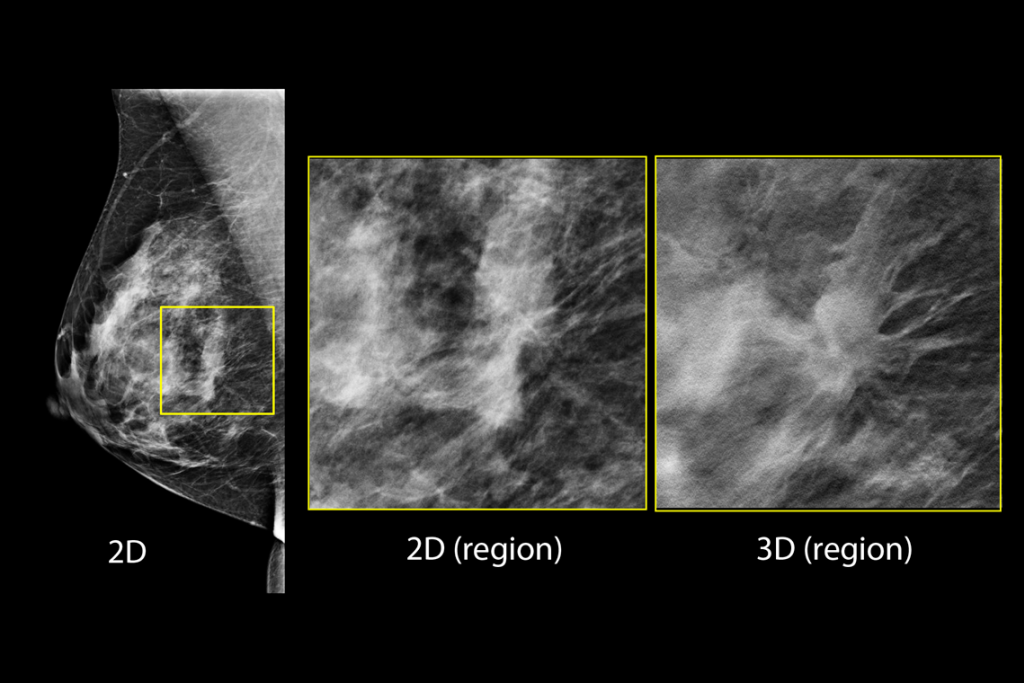

3Dimensions マンモグラフィシステムでは、Clarity HD™ 高解像度イメージング、Intelligent 2D™ Imaging テクノロジー、3DQuorum® SmartSlice を組み合わせたスマートトモシンセシステクノロジーが採用されており、効率的なワークフローが実現します。

乳房検査マンモグラフィの臨床画像

疑わしい病変が見られる乳房検査の臨床画像